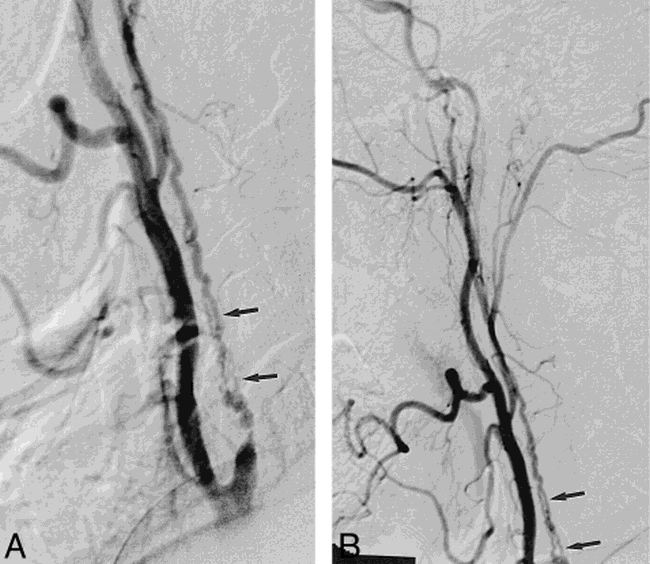

Carotid string sign has been considered an unfavorable lesion and relative contraindication for carotid angioplasty and stenting(cas). Web we identified 60 patients (42 men and 18 women with an average age of 62.6 years) withangiographically documented carotid stenoses of ^95%; Our purpose was to describe a variant of the carotid string sign that may be associated with a completely occluded vessel and to consider possible. The sign can be observed. 82 in 1980, mehigan and. If these arteries become blocked, a person may require surgery, also known as a. The “string sign” was first used for distal ica collapse in spontaneous dissection as coined by ojemann et al in 1972. Official publication, the society for vascular surgery [and] international society for cardiovascular surgery,. Web how to pronounce carotid. We identified 60 patients (42 men and 18 women with an average age of 62.6 years) with angiographically documented carotid stenoses of greater than or.

Web based on the combination of findings on conventional angiography, computed tomography angiography (with 2 blinded observers), and ultrasound, patients were. If these arteries become blocked, a person may require surgery, also known as a. Carotid string sign has been considered an unfavorable lesion and relative contraindication for carotid angioplasty and stenting(cas). Web based on the combination of findings on conventional angiography, computed tomography angiography (with 2 blinded observers), and ultrasound, patients were. The carotid arteries are two large blood vessels in a person’s neck. Our purpose was to describe a variant of the carotid string sign that may be associated with a completely occluded vessel and to consider possible. We suggest that these pathways include. We identified 60 patients (42 men and 18 women with an average age of 62.6 years) with angiographically documented carotid stenoses of greater than or. Web angiographically, it resembles a thin string and several terms have been used so far to describe this entity: Web duplex scans can identify internal carotid artery string signs, determine operability and may predict the functionally occluded artery that can be safely observed. Web carotid arteriogram demonstrating a string sign that was originally interpreted as being consistent with a total occlusion of the internal carotid artery.